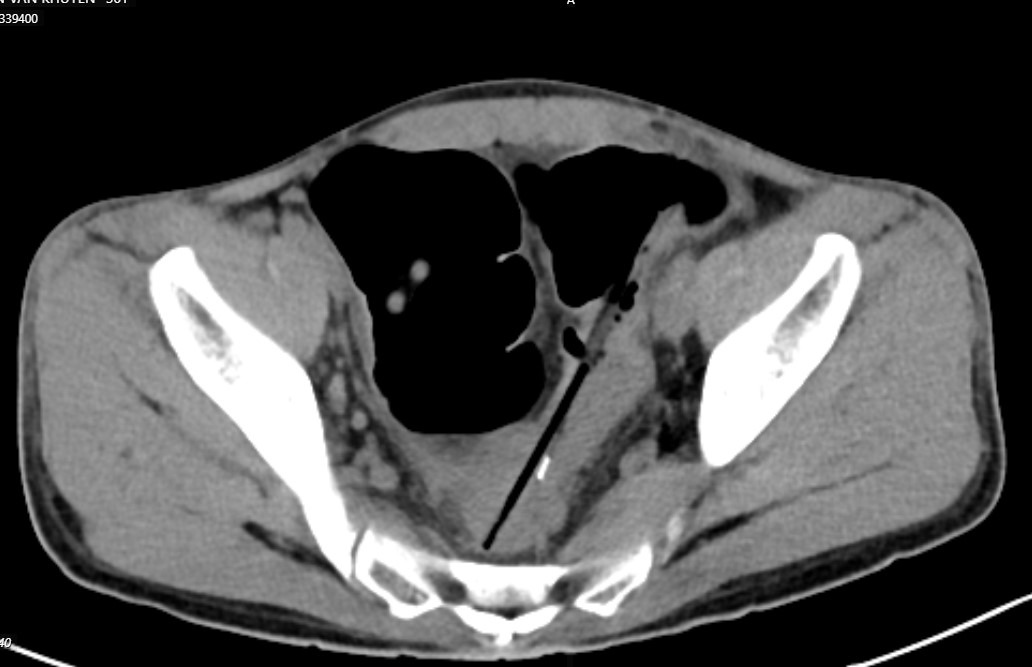

Chụp cắt lớp ổ bụng thấy hình ảnh 2 dị vật hình que đầu kim loại trong quai ruột vùng hạ vị, đâm xuyên thành ruột tạo ổ dịch khí vùng tiểu khung cạnh cơ bịt phải; Dị vật trong quai ruột hạ sườn phải; Dày thành trực tràng, đại tràng sigma và quai ruột ngang rốn; Giãn lan tỏa các quai ruột non.

Hình ảnh chiếu chụp cho thấy nhiều dị vật trong bụng bệnh nhân. Ảnh BVCC